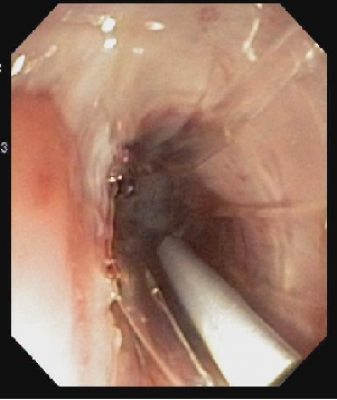

Thắt tĩnh mạch thực quản

Nội soi thắt tĩnh mạch thực quản ra đời sau tiêm xơ, được ưa chuộng hơn. Tuy nhiên, dụng cụ có kích thước tương đối lớn nên đôi khi khó áp dụng ở trẻ nhỏ.